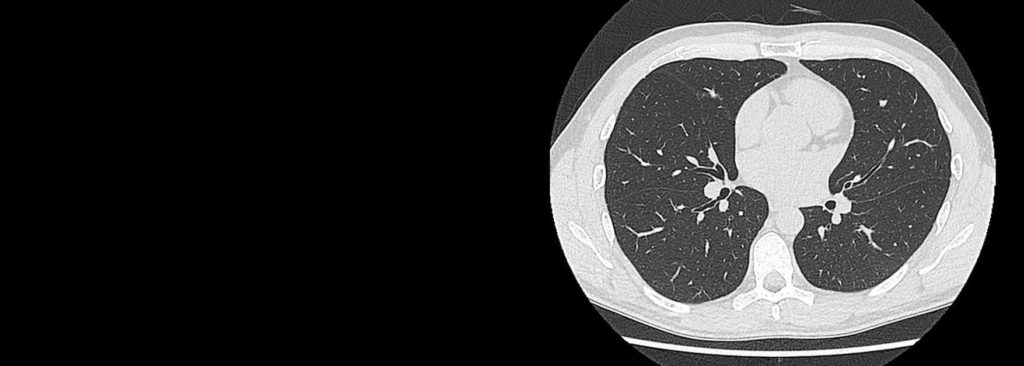

Idiopathic Pulmonary Fibrosis (IPF) is a chronic, progressive, irreversible, unpredictable and incurable disease that kills the same number of people every year as breast cancer. Yet, IPF remains an unknown disease that receives little attention resulting in a lack of innovative solutions, research, patient resources, and funding that is desperately needed. But with Three Lakes Partners, all that changes now.

Diagnosis of IPF is difficult, as it relies upon the process of elimination. Because of this, it takes an average of 26 months for a patient to be diagnosed with IPF. This delay in diagnosis can take a significant physical and emotional toll on the patient’s well-being. That’s why Three Lakes Partners is dedicated to funding and fueling innovative diagnostics and devices to incite the brightest minds to make faster strides towards IPF diagnoses.